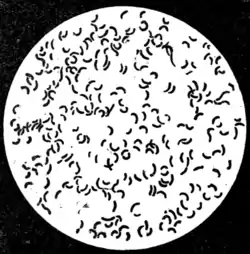

Description of the comma bacillus.—The comma bacillus (Fig. 77) is a very minute organism, 1.5 to 2 μ in length by 0·5 to 0·6 μ in diameter—about half the length and twice the thickness of the tubercle bacillus. It is generally slightly curved, like a comma; hence its name. After appropriate

Fig. 77.—Cholera bacillus. Agar culture: 24 hours' growth.

x 1,000. (Muir and Ritchie.)

staining, at each end, or at one end only, flagella can be distinguished—sometimes one, sometimes (though less frequently) two. These flagella, though of considerable length—from one to five times that of the body of the bacterium—owing to their extreme tenuity are difficult to see in ordinary preparations. They are not always present during the entire life of the parasite. In virtue of this appendage the bacillus exhibits very active spirillum-like movements. The individual bacilli when stained show darker parts at the ends or at the centre, suggesting spore formation. Sometimes in tions two or more bacilli are united, in which case an S-shaped body is the result; or it may happen that several bacilli are thus united together, producing a spirillar appearance.